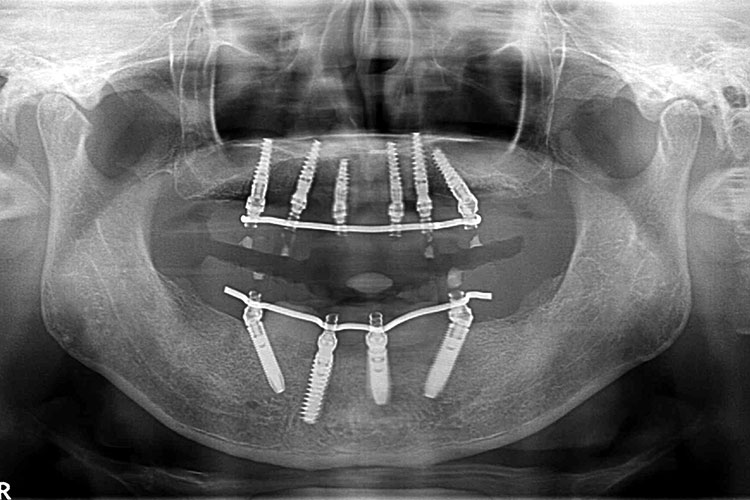

難症例のインプラント治療例【10本】

患者様

情報

治療期間

治療費

埋入数

リスクと副作用

男性

10ヶ月

5,637,600円

10本

術後に痛みや

腫れが出る恐れ